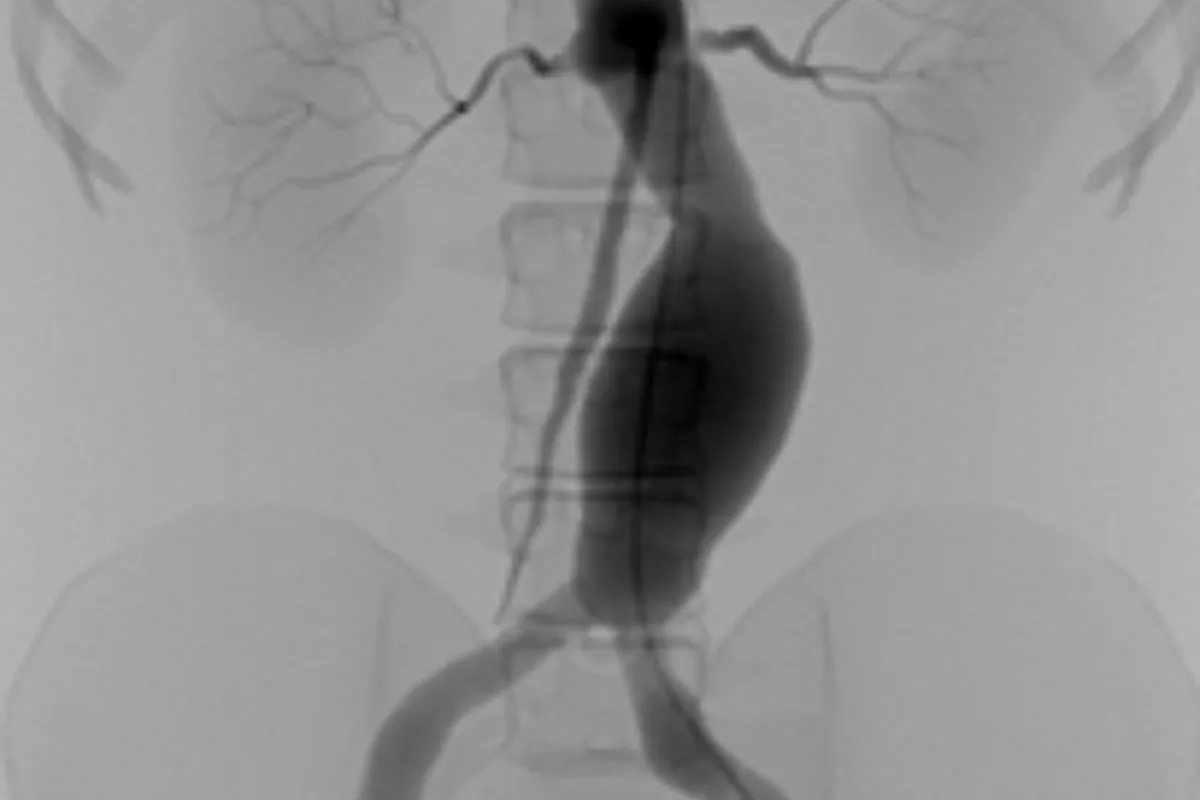

Interventional Radiology (IR) uses real-time imaging such as X-ray, ultrasound, CT, or MRI to guide tiny instruments through the body for treatment — without large surgical incisions.

Common Interventional Radiology Procedures